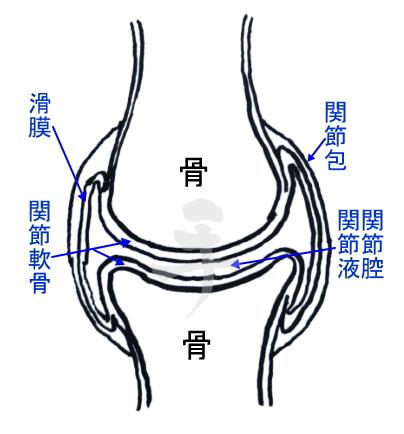

滑膜関節

一般的に『関節』として認識されている関節(狭義の関節)。

滑らかな骨端の関節面を更に滑らかに覆う関節軟骨(硝子軟骨)と、関節液で満たされた関節包がある。とにかく『動かすための構造』なのが滑膜関節。

関節軟骨は約70%の水分とⅡ型コラーゲンとプロテオグリカン(糖タンパク)が主成分。血管や神経線維の分布はないので関節自体が痛みの発信源になることはありません。